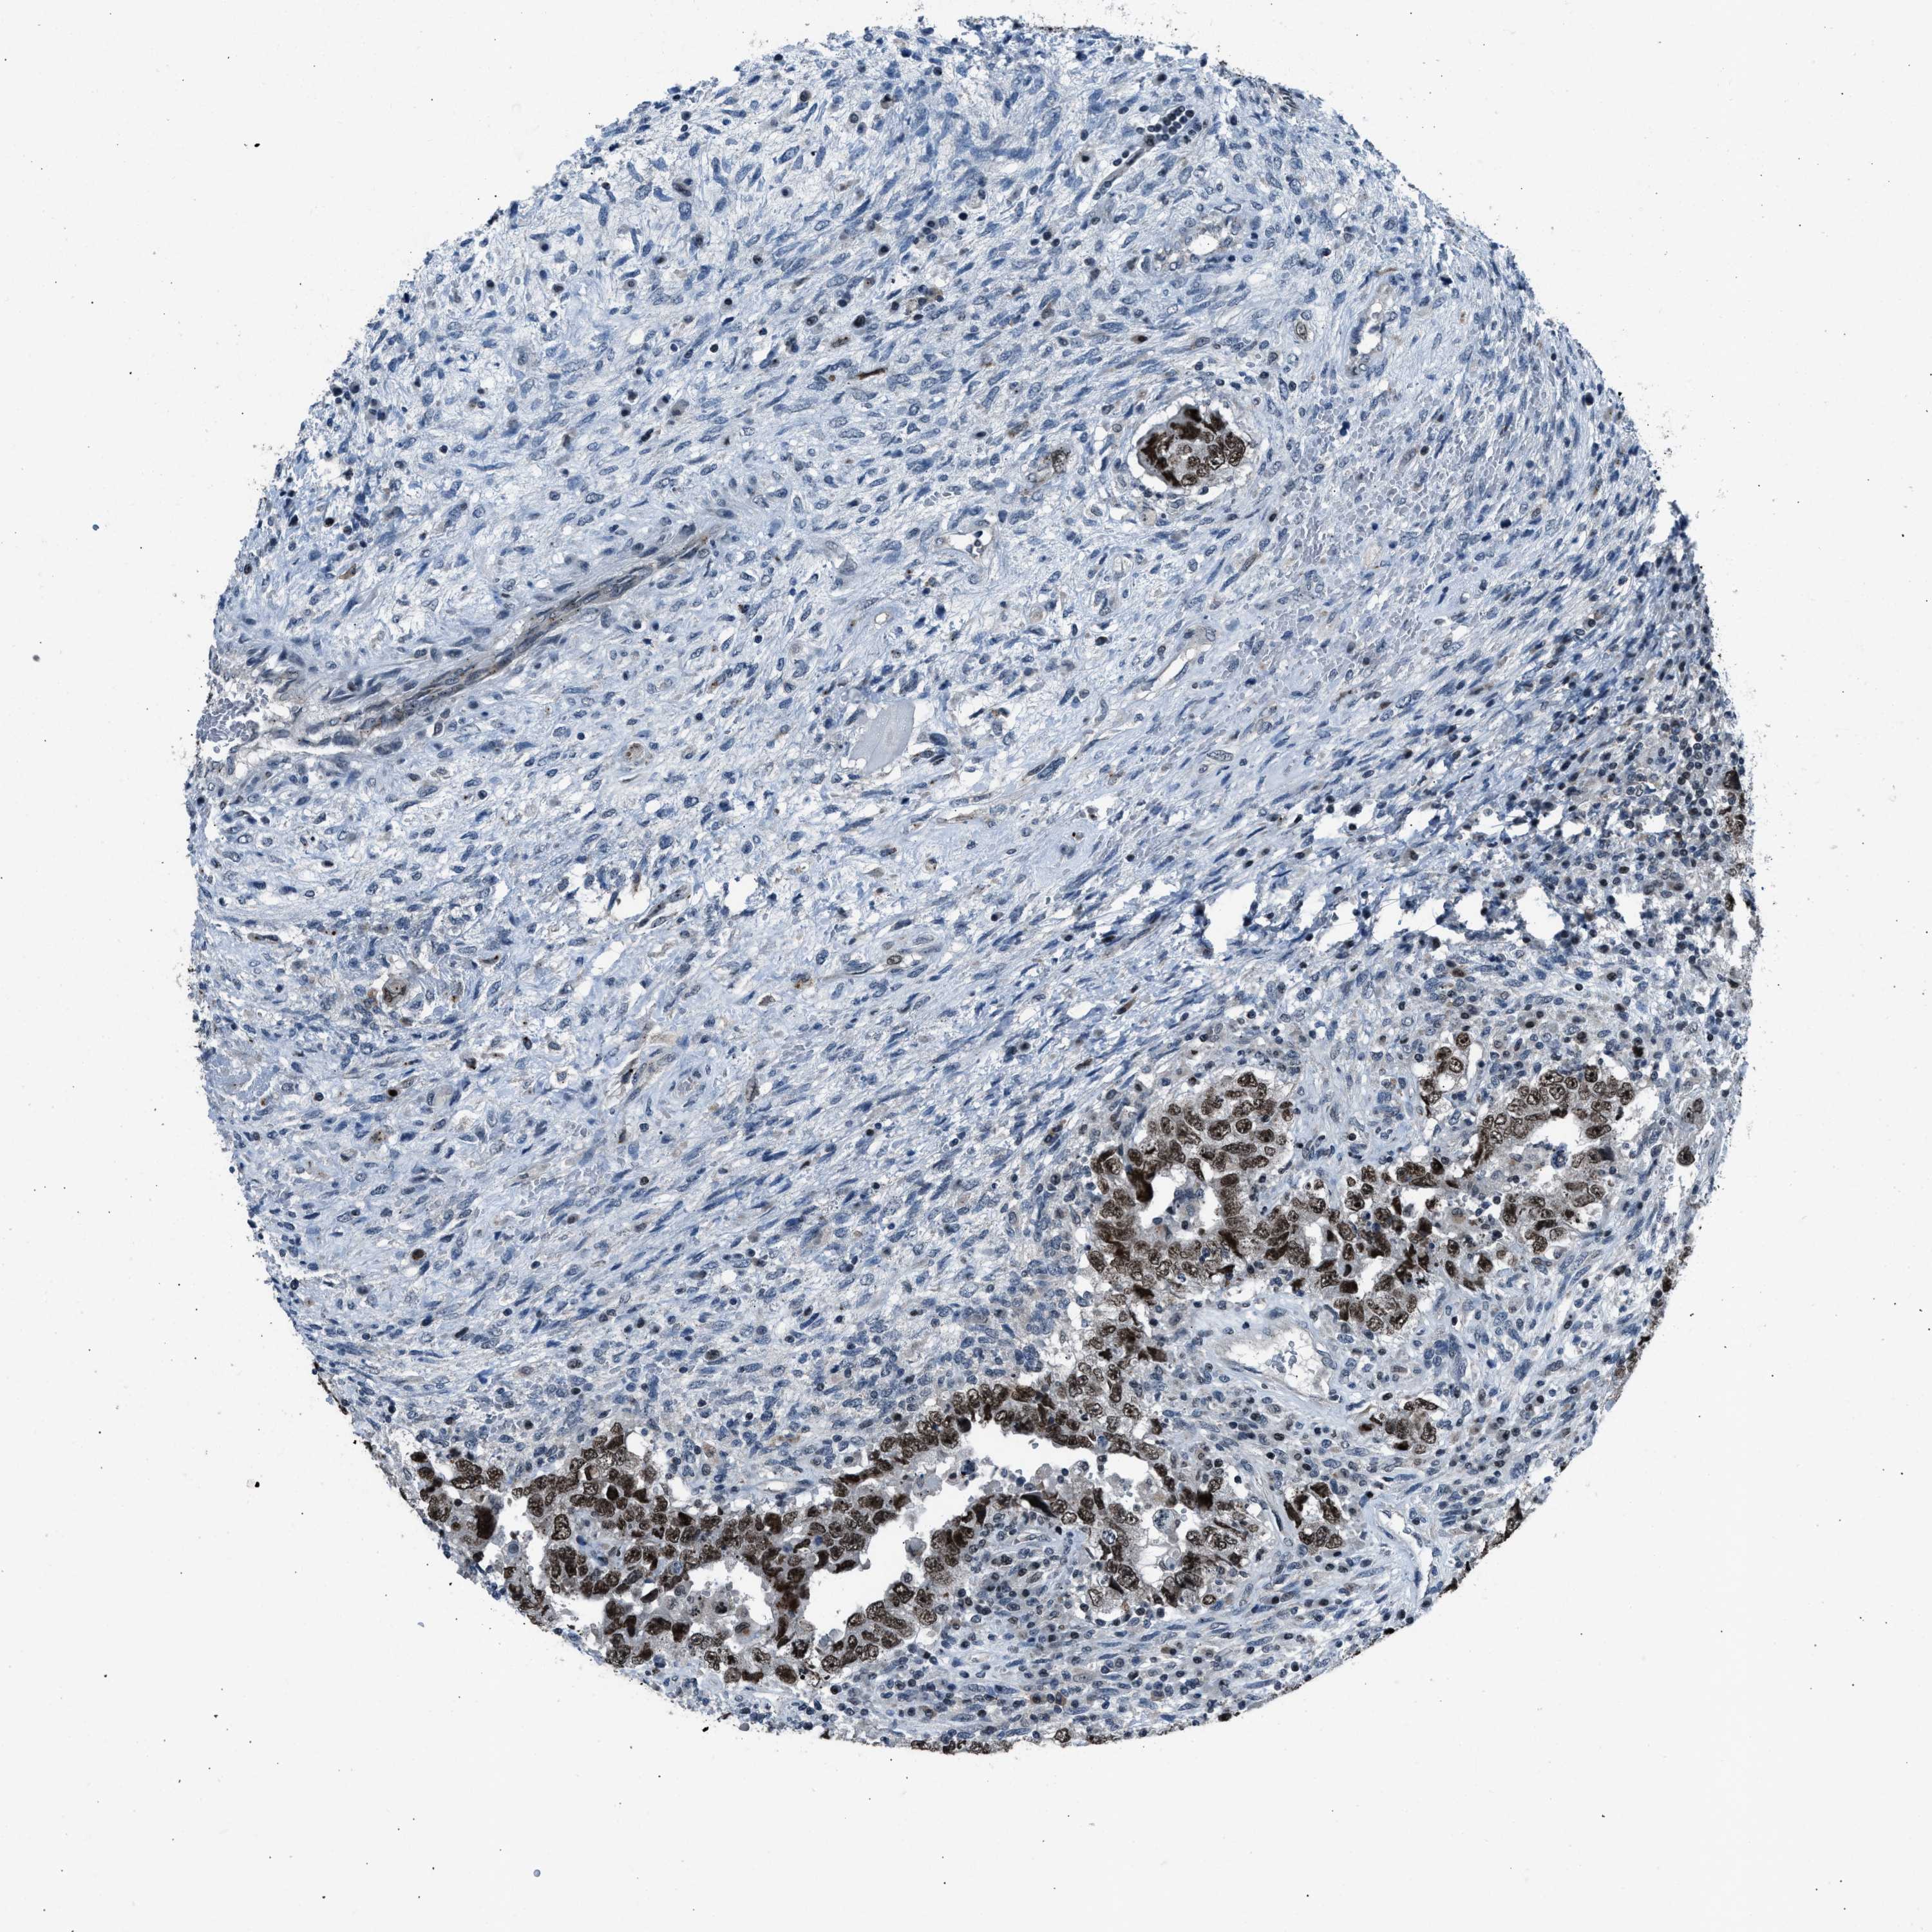

TESTIS CANCER - Protein expressioni

A mouse-over function shows sample information and annotation data. Click on an image to view it in a full screen mode. Samples can be filtered based on level of antibody staining by selecting one or several of the following categories: high, medium, low and not detected. The assay and annotation is described here.

Note that samples used for immunohistochemistry by the Human Protein Atlas do not correspond to samples in the TCGA dataset.

Antibody stainingi

Antibody staining in the annotated cell types in the current human tissue is reported as not detected, low, medium, or high, based on conventional immunohistochemistry profiling in selected tissues. This score is based on the combination of the staining intensity and fraction of stained cells.

Each image is clickable and will lead to virtual microscopy that enables deeper exploration of all samples and also displays staining intensity scores, fraction scores and subcellular localization as well as patient and tissue information for each sample.

Antibody CAB018364

Staining

High

Medium

Low

Not detected

Intensity

Strong

Moderate

Weak

Negative

Quantity

>75%

75%-25%

<25%

None

Location

Nuclear

Cytoplasmic/membranous

Cytoplasmic/membranous,nuclear

Carcinoma, Embryonal, NOS